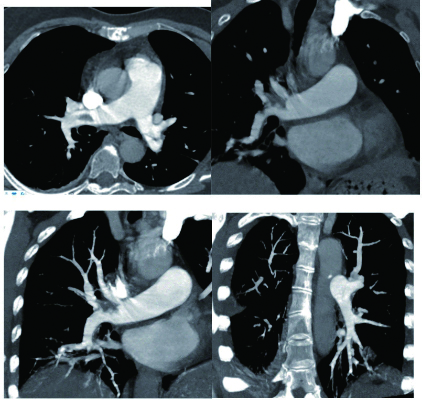

2 积极寻找补救性溶栓的治疗时机并非遥不可及例3 36岁,女性。主诉“活动后气短5 d、加重伴咯血1 d”。既往因月经不调,应用激素替代治疗20 d;否认手术、外伤及制动史。入院查体:神志清楚,体温36.8℃,血压110/75 mmHg,脉率118次/min,呼吸23次/min,脉氧饱和度90%(安静,空气氧),轻度乏氧征。双肺呼吸音清。心率118次/min,未闻及干、湿性啰音,心律齐,P2 > A2,心界无扩大,无杂音,腹软,无压痛,肠鸣音正常,双下肢无浮肿。神经系统查体未见异常。血气分析(空气氧)提示pH 7.415,PaCO2 38.3 mmHg,PaO2 89.90 mmHg,SaO2 89.90%;D-Dimer 1 684 ng/mL;FDP 8.670 μg/mL,FBG 3.510 g/L;PLT 151.0 G/L;cTnI 0.00 ng/mL,BNP 58.00 ng/mL;ALT 27 U/L,AST 17 U/L,CREA 53.7 μmol/L,血Na+、K+、Cl-大致正常;UCG提示:右室壁运动减低,左室壁运动不协调,各室壁厚度正常,三尖瓣环位移14 mm,右室面积变化率19%,各瓣膜形态及运动未见异常,收缩期三尖瓣房侧见少量反流信号,T1法估测SPAP:24 mmHg;双下肢静脉超声提示:右下肢深静脉血栓形成。心电图(图 8所示)提示窦性心动过速;CTPA提示双肺主干明确充盈缺损(图 9所示)。入院诊断:急性PE(中低危)。给予低分子肝素抗凝治疗。入院24 h内,大便时出现胸闷、心悸主诉,SpO2由93%(不吸氧)降至88%(储氧面罩吸氧,Flow 10 L/min);D-Dimer由入院时1 026 ng/mL升至4 100 ng/mL,血压110/70 mmHg。因血氧有恶化趋势遂决定给予静脉溶栓治疗(r-tPA 50 mg,2 h内泵入),溶栓治疗结束后2 h复查凝血提示D-Dimer 45 000 ng/mL。溶栓2 h患者症状明显好转;心电图提示窦性心动过速,SⅠQⅢTⅢ征象较前改善,胸前导联出现冠状T波(图 10所示)。溶栓后24 h复查CTPA右肺主干血栓明显消失,右心室较前明显缩小(图 11所示)。

| 图 9 入院时CTPA提示右肺动脉主干充盈缺损、左肺亚段水平充盈缺损、右心室增长 |

| 图 11 溶栓后CTPA提示原有血栓完全溶解、右心室较前明显缩小 |

患者特点及再灌注治疗时机选择:这是一例中高危PE患者接受抗凝治疗期间,大便后出现血氧改变但尚未出现血流动力学变化时,接受了补救性溶栓治疗并成功的案例。患者入院后出现的病情变化主要以缺氧程度加重为主,并没有血流动力学不稳定表现。提供补救性系统溶栓治疗出于两方面的考虑:①排便前后(床上)血氧出现很大的变化;②D-Dimer有升高趋势,警惕凝血和纤溶动态平衡的再次激活;③入院时CTPA血栓负荷较大,一旦血栓再次脱落可能会引发致命性的血栓事件发生。溶栓治疗后患者症状明显缓解、CTPA明显改善及溶栓2 h的心电图T波加深均提示溶栓治疗成功。